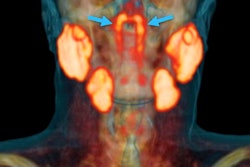

- Head and neck cancer (8.0%)

- Malignant bone disease (2.4%)